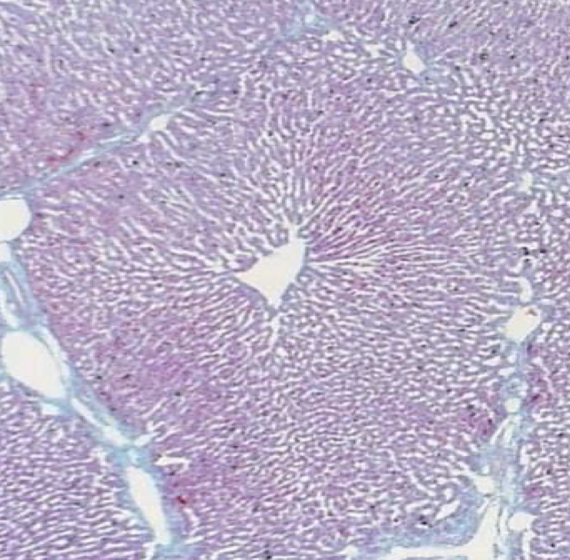

What does the blue in this picture represent (and function)? What is the border at the very bottom of the image (and function)?

Blue represents CT of type III collagen, or the STROMA. The peritoneum/serosa at the bottom with some CT is Glisson’s capsule.

What is shown in the image? What is the hole in the middle? what is the shape?

Lobule of a pig liver (to see better). Each lobule has a hole in the middle, which is the central vein. The shape is polyganol/hexagonal surrounded by portal triads.

Name the feature

Type III collagen (reticular fibers), silver stain